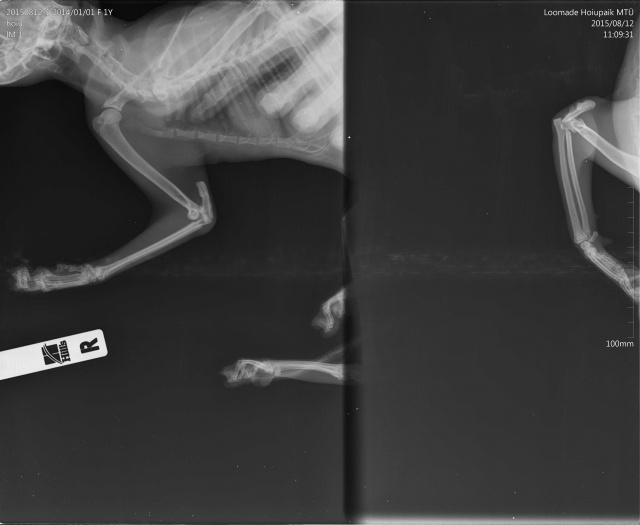

Диагноз:

- вывих локтевого сустава

- перелом локтевой кости

- межмыщелковый перелом плеча(?)

Esikäpa vigastusega.